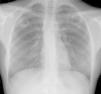

Mujer de 24 años, caucásica, fumadora de 5 cigarros al día, sin antecedentes médicos y de profesión periodista. Desde hace 3 meses presenta expectoración purulenta, sin otra sintomatología asociada, que no desaparece con distintos ciclos de tratamiento antibiótico. Refiere contacto, en ámbito laboral en Londres 20 meses antes, con persona afecta de tuberculosis (TBC) y el año pasado contacto esporádico con una amiga diagnosticada de TBC. En ambos casos no se realiza estudios de contactos. Ante la persistencia de la sintomatología se solicita radiografía torácica objetivándose 2 imágenes cavitadas en ambos lóbulos superiores, prácticamente simétricas y bien delimitadas (fig. 1). La tinción de auramina fue positiva y en el cultivo se aisló Mycobacterium tuberculosis. La serología de virus hepatotropos y virus de la inmunodeficiencia humana fue negativa.

No hay ningún signo ni patrón radiográfico patognomónico de TBC. El espectro radiológico es amplio, aunque sí es cierto que pueden reconocerse algunos patrones muy sugestivos como es el caso de cavernas en lóbulos superiores. En la mayoría de los casos estas cavidades suelen ser multifocales y con paredes gruesas e irregulares1,2, en cambio, en el caso que presentamos se objetivan 2 cavernas aisladas, bilaterales y bien definidas, una presentación cuanto menos curiosa.